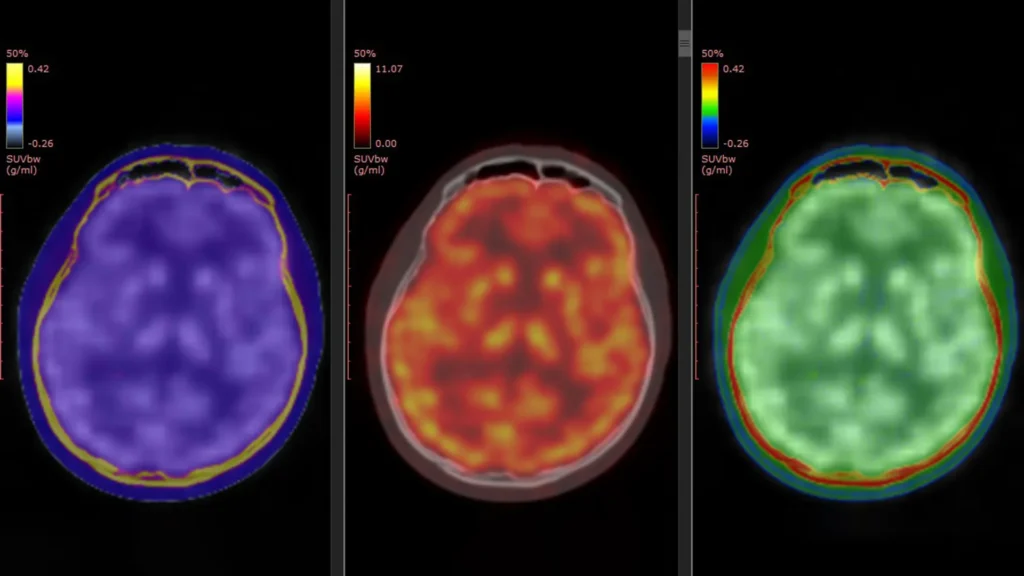

Brain scans reveal how ketamine quickly lifts severe depression